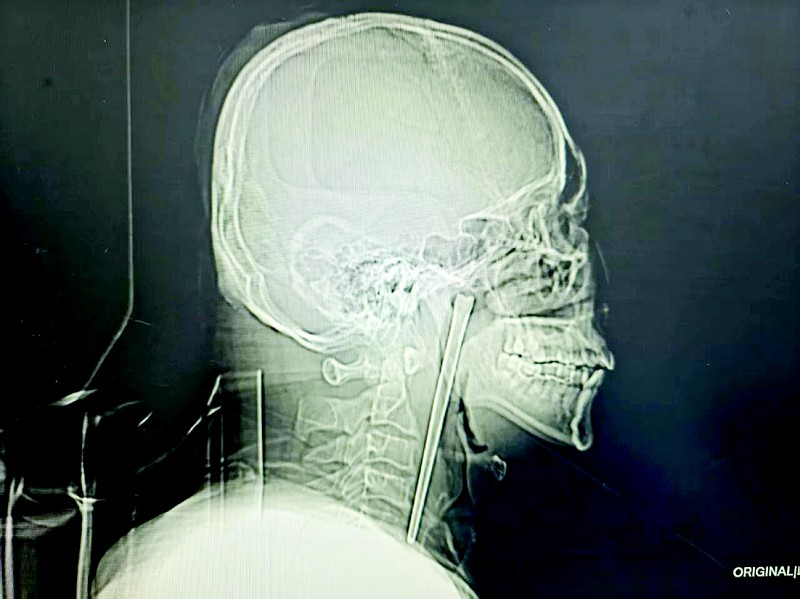

近日,46岁的王先生(化名)因咽部突发疼痛、异物感难忍,前往大连理工大学附属中心医院(大连市中心医院)耳鼻咽喉头颈外科就诊。检查结果让人大吃一惊:一根长达12厘米的金属筷子竟滞留在他的咽部整整8年。最终,该院医疗团队通过微创手术成功将其完整取出,为患者解除了多年的健康隐患。

接诊的黄巍鹏医生详细询问病史后,立即为其安排电子喉镜检查。检查结果显示,王先生右侧咽后壁黏膜下、软腭后侧有一根金属筷子嵌入,肉眼可见部分约3厘米。

在刘得龙的指导下,黄巍鹏为王先生定制经口腔取异物的微创手术方案,这种无需颈部开刀的治疗方式,彻底打消了患者的顾虑。术中,医生精准定位,巧妙避开咽部的重要血管和神经,通过微创手术逐步剥离、牵拉,最终将这根12厘米的不锈钢筷子完整取出。术中出血量极少,无手术并发症,患者和家属悬着的心终于落地。